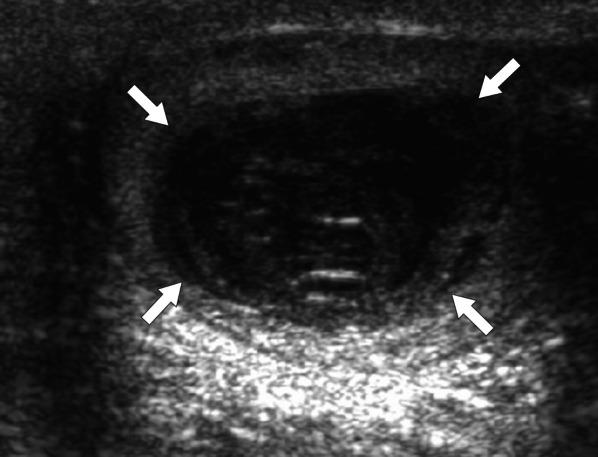

Identifying the deceiver: the non-neoplastic mimickers of genital system neoplasms.

Tumors of the genital system are common and imaging is of crucial importance for their detection and diagnosis. Several non-neoplastic diseases may mimic these tumors and differential diagnosis may be difficult in certain cases. Misdiagnosing non-neoplastic diseases as tumor may prompt unnecessary medical treatment or surgical interventions. In this article, we aimed to present the imaging characteristics of non-neoplastic diseases of the male and female genital systems that may mimic neoplastic processes. Increasing awareness of the imaging specialists to these entities may have a severe positive impact on the management of these patients.